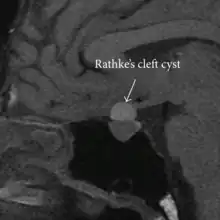

Rathke's cleft cyst

Rathke's cleft cyst in a 53-year-old man with a pituitary adenoma and acromegaly

A Rathke's cleft cyst is a benign growth on the pituitary gland in the brain, specifically a mucin-filled[1] cyst in the posterior portion of the anterior pituitary gland.[2][3] It occurs when the Rathke's pouch does not develop properly and ranges in size from 2 to 40 mm in diameter.[3]